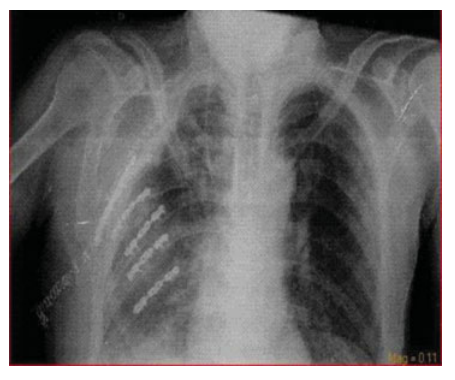

一名53岁的男性患者,因高处掉落的建筑材料砸中右肩和胸部区域而被送往急诊科。初步体检显示患者右肩部有表皮擦伤和广泛的皮下气肿,右前胸壁有一大约10×15 cm的连枷胸区域,并伴有呼吸困难。胸片显示右侧多根肋骨、锁骨和肩胛骨骨折,右侧液气胸以及广泛的皮下气肿(►图1和图2)。

图1. 患者置入胸腔引流管后的胸片。